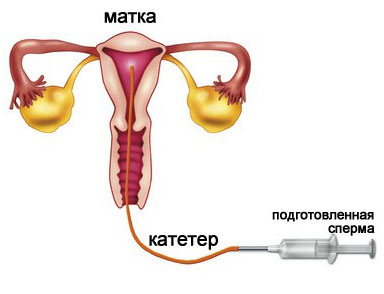

Инсеминация, или искусственная инсеминация – это медицинская процедура, которая проводится при невозможности пары или женщины самостоятельно зачать ребенка. В ходе инсеминации в полость матки при помощи катетера вводят мужскую сперму или обработанные сперматозоиды. Сперму обычно берут либо у супруга или партнера женщины, либо донорскую.

Начинают процедуру с взятия рабочего материала, т.е. мужской спермы примерно за два часа до самой процедуры. Иногда используют замороженную сперму, обычно, при использовании донорского материала. Чаще всего перед процедурой сперму обрабатывают (а иначе процент на успех значительно снижается), и вводят в полость матки.

Проводится инсеминация перед овуляцией, либо естественной, либо вызванной путем стимуляции. Отслеживают овуляцию либо с помощью тестов, либо при помощи УЗИ. За один цикл инсеминацию повторяют трижды. Через две-три недели при благоприятном исходе процедуры тесты на беременность будут положительными.

При инсеминации подготовленные сперматозоиды вводят в маточную трубу, после чего все происходит естественным образом, как и задумано природой: наиболее сильный и быстрый оплодотворяет яйцеклетку, которая затем опускается и закрепляется на стенках матки. При ЭКО в организм женщины переносят уже развивающиеся эмбрионы.